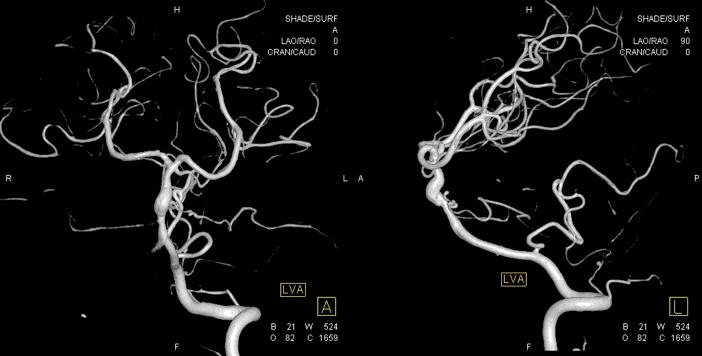

本院 DSA三维血管重建(2019-10-10)显示:基底动脉巨大夹层动脉瘤(图7)。

图7